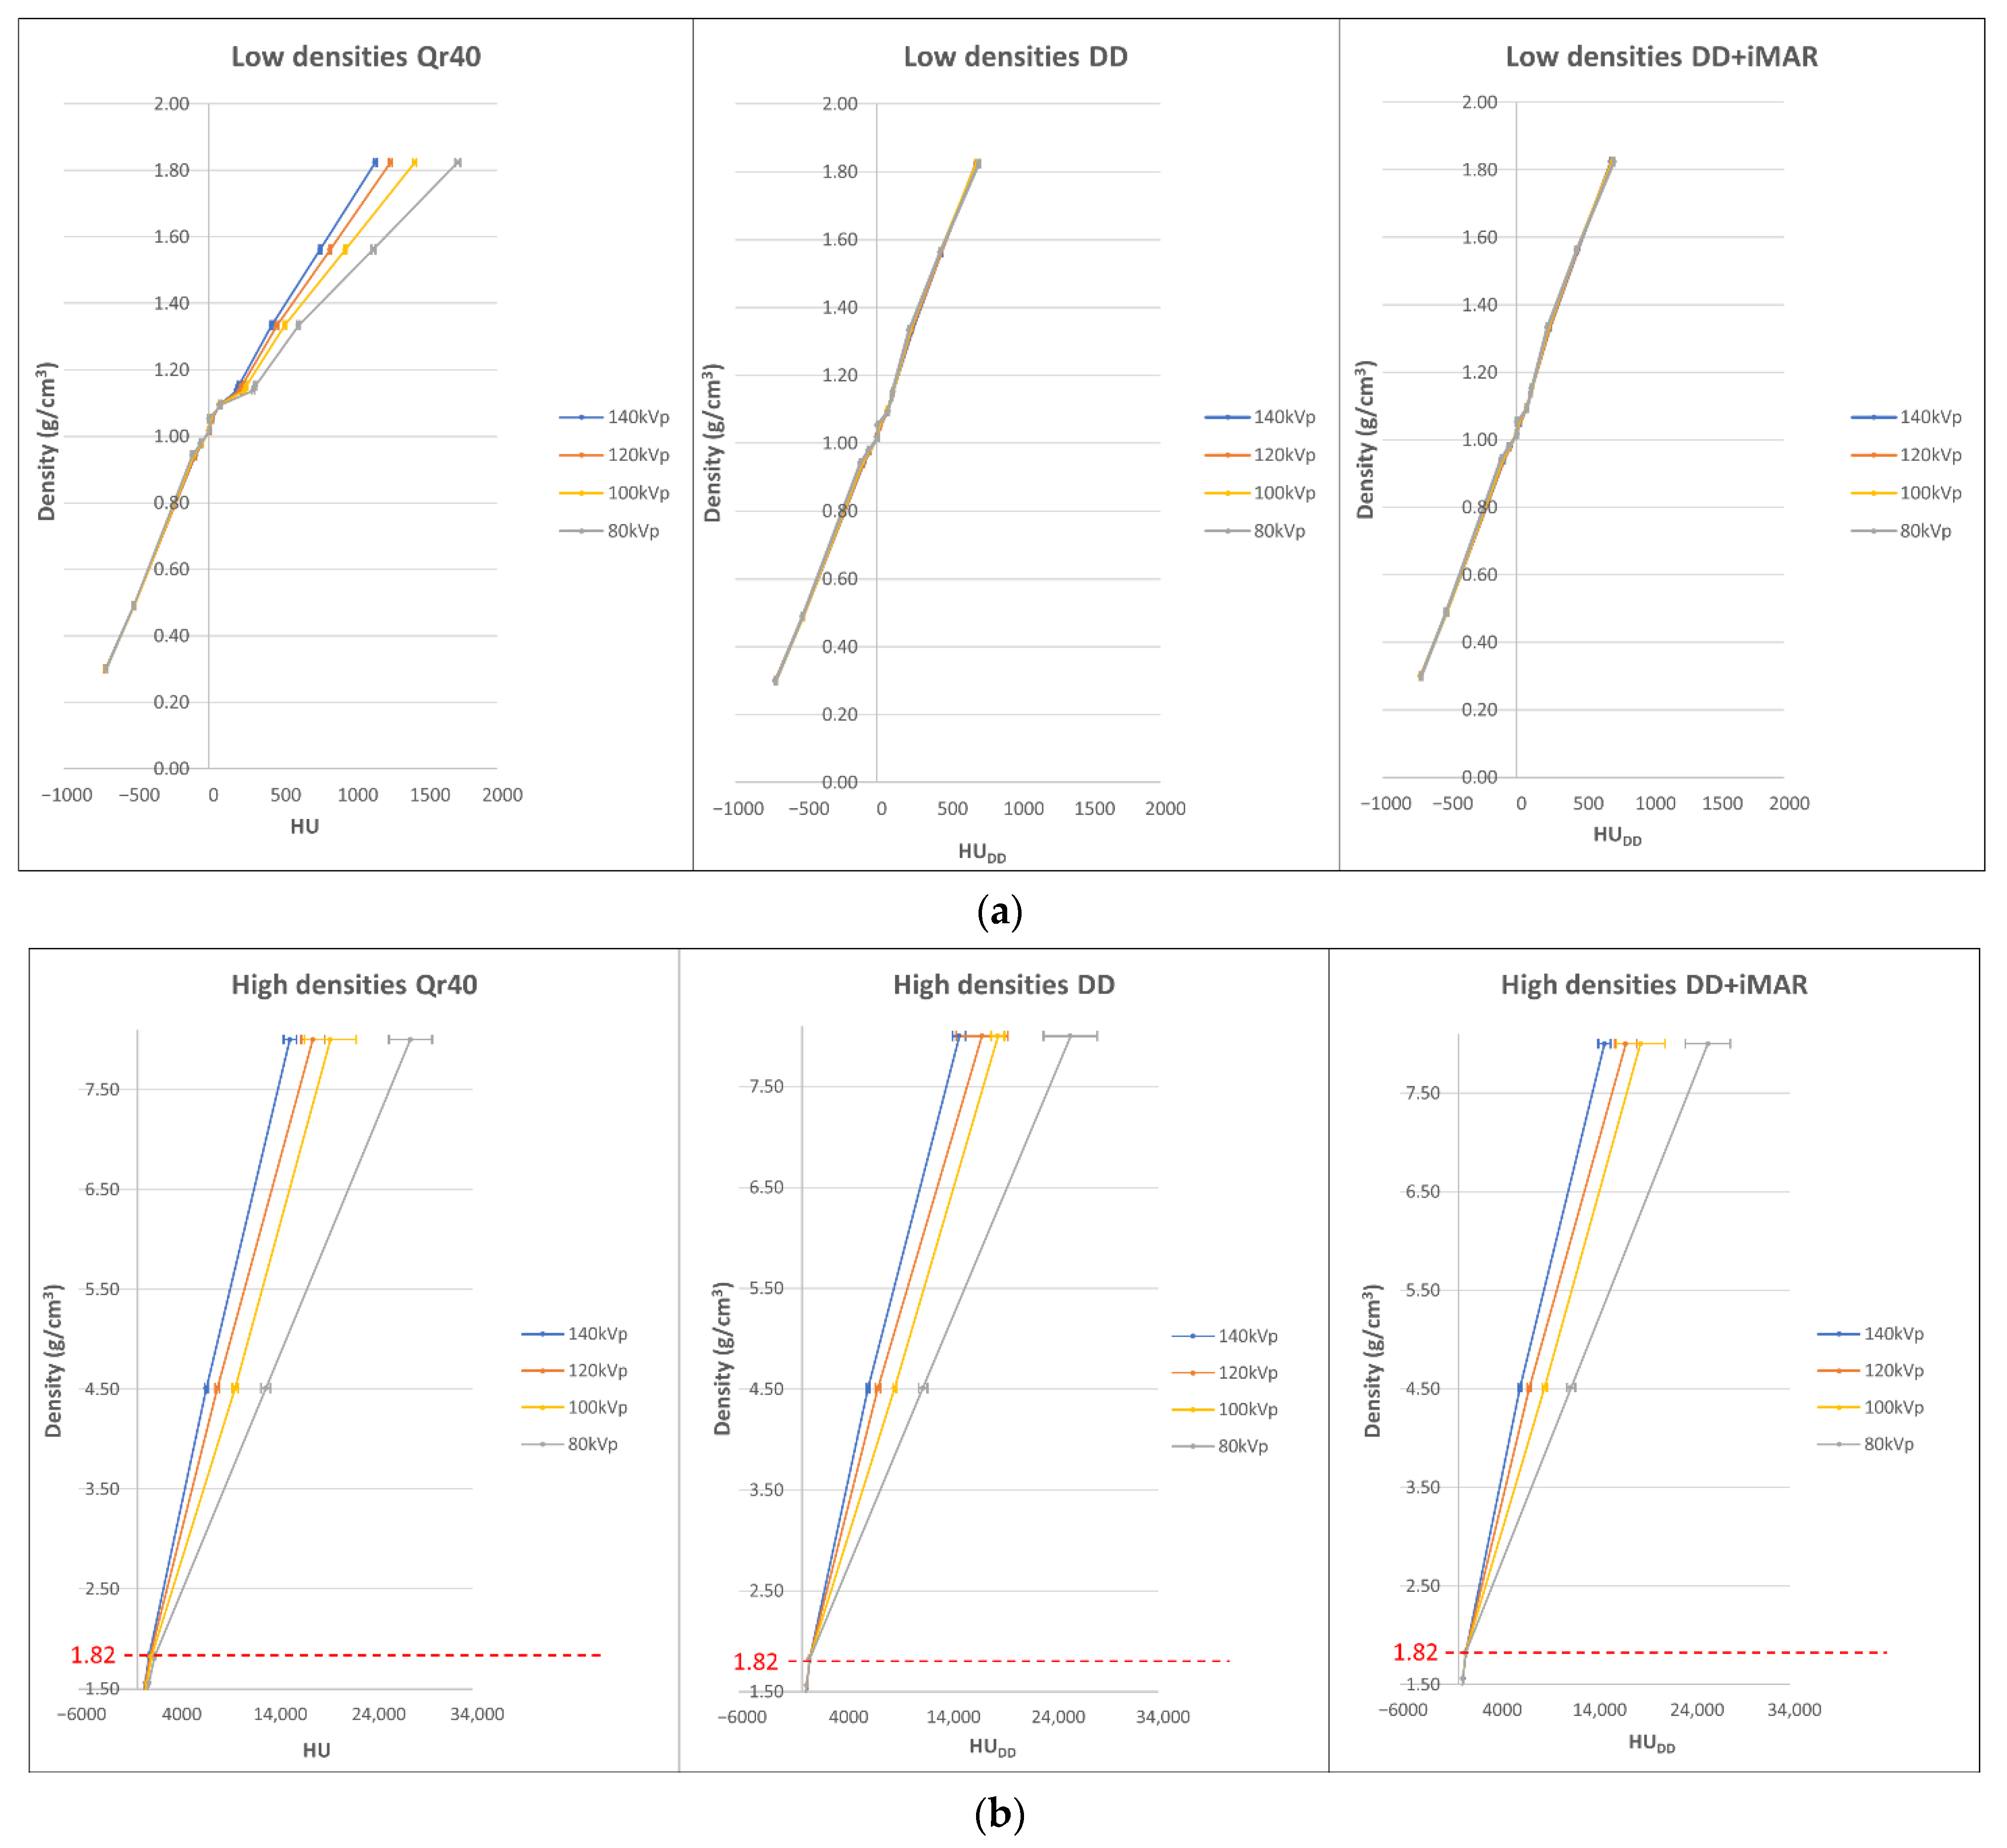

2.2. Calibration Curve Building

3.1. Curve Building and Metal Artifact Influence on Non-Metal ROIs

3.2. Mean Calibration Curves